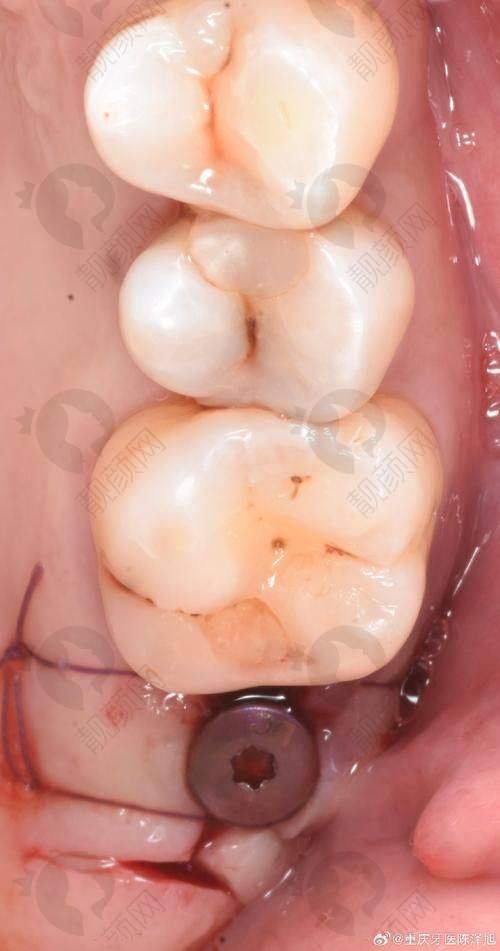

还有一位50多岁的女士,从东北来到上海鼎植口腔。她对种植牙的舒适程度和美学要求都特别高,前期手术方案几经取舍才敲定。在手术过程中,徐九波医生与高振华院长配合默契,始终关注患者的舒适程度。手术非常顺利,这位女士戴上牙之后,整个人状态大不相同,对种植牙成效十分满意。